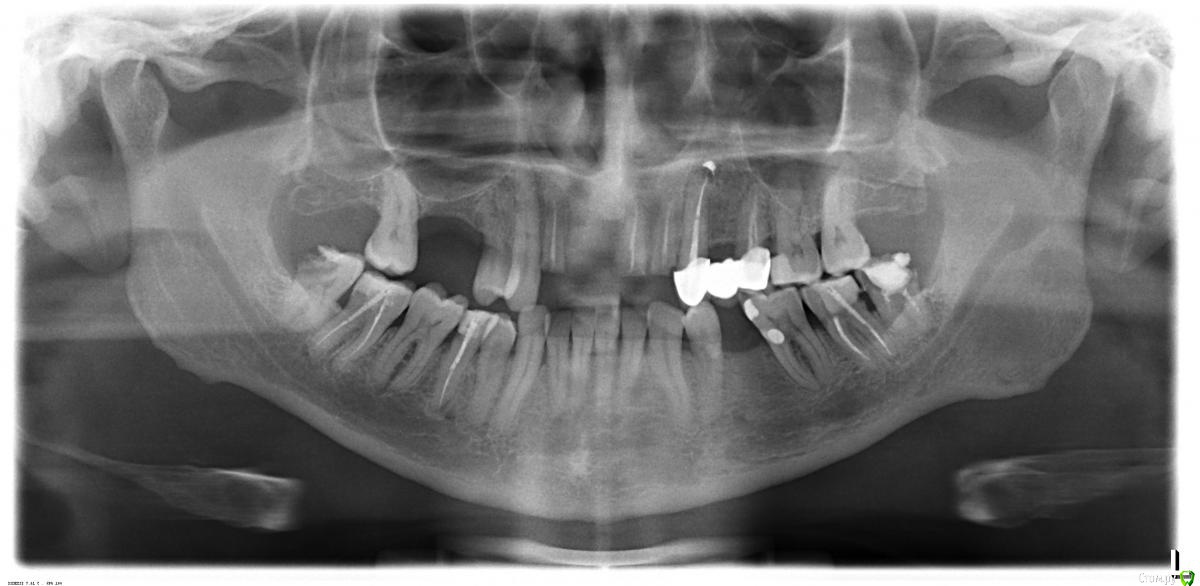

kozloff Опубликовано 12 декабря, 2015 Поделиться Опубликовано 12 декабря, 2015 Какие есть варианты практичного и долговременного протезирования в моем случае? Имплантация. Корни 12, 21, 22 на удаление Где, у кого и с каким бюджетом это лучше сделать в Москве? http://forum.stom.ru/topic/9249-posovetujte-ortopeda-v-gorode-n/page-28 Сейчас хочу обратиться в другую клинику. Хорошее решение 1 Ссылка на комментарий

DDD137 Опубликовано 13 декабря, 2015 Автор Поделиться Опубликовано 13 декабря, 2015 Большое Вам спасибо за ответ. Предложили переделать мост, но уже на вкладках. ( В другой клинике).Не знаю насколько это может быть долговременным и практичным решением. Чем на Ваш взгляд 4 импланта с удалением 3 корней лучше? Или м.б. вариант моста на вкладках с имплантом 11? Мне 48 лет. Еще раз ОГРОМНОЕ СПАСИБО за Ваше мнение Ссылка на комментарий

chervoncevdaniil Опубликовано 13 декабря, 2015 Поделиться Опубликовано 13 декабря, 2015 Так же в руках через годик принесете мост на вкладках,там нет достаточного количества твердых тканей,чтобы конструкция долго функционировала.Долговременный результат-имплантация(при условии грамотного хирурга и ортопеда) 2 Ссылка на комментарий